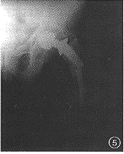

例5男,67岁,左侧全髋关节置换术后7年。入院前1个月突然出现大腿部疼痛,X线片示假体股骨柄断裂,股骨假体近端内翻,骨水泥周围有透亮区形成。手术中见髋臼前、后柱完整,内侧壁容积性骨缺损,股骨假体近端松动,远端假体柄断裂(图5)。

图1男,72岁,右全髋关节置换术后5年。右股骨假体内翻下沉,假体远端骨水泥断裂,髋臼假体周围有连续的透亮区图2女,65岁,人工股骨头置换术后5年。髋臼内壁磨损,容积性骨缺损图3女,68岁,右侧人工股骨头置换术。假体外翻位,假体柄自内侧骨皮质穿出图4男,40岁,股骨颈骨折后股骨头缺血性坏死。行人工股骨头置换术,人工股骨头过度前倾位置入图5男,67岁,左侧全髋关节置换术后7年。假体股骨柄断裂,股骨假体近端内翻,骨水泥周围透亮区形成图6男,62岁,左侧全髋关节置换术后4年。髋臼假体金属杯与聚乙烯内衬脱位,髋臼金属假体与股骨假体直接接触